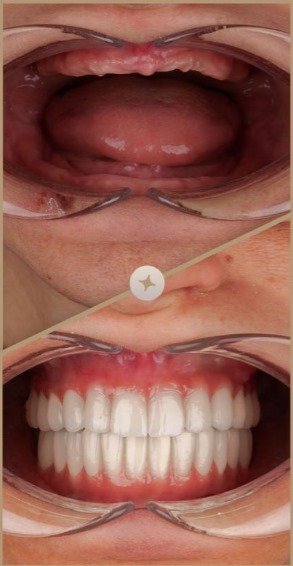

Presso la ES Dental Albania, comprendiamo quanto sia importante il tuo sorriso per la tua autostima e il tuo benessere. Quando perdi un dente, non si tratta solo dell’aspetto esteriore—può influire sulla tua capacità di parlare, mangiare e goderti la vita appieno. È qui che entra in gioco l’Implantologia Dentale. Gli impianti dentali sono una soluzione rivoluzionaria progettata per sostituire i denti mancanti con risultati naturali e duraturi.

Il nostro team di esperti è specializzato nel fornire impianti dentali di alta qualità che ripristinano sia la funzionalità che l’estetica, restituendoti il sorriso che meriti. Lasciaci aiutarti a recuperare la tua autostima con un trattamento sicuro ed efficace.

A differenza delle tradizionali protesi o ponti, gli impianti dentali sono progettati per funzionare come denti naturali. Offrono una base sicura e stabile, permettendoti di mangiare, parlare e sorridere con facilità. Che tu stia perdendo un solo dente o diversi, gli impianti offrono una soluzione durevole e affidabile.

– Aspetto Naturale: Gli impianti sono progettati per sembrare e sentirsi come denti naturali, integrandosi perfettamente con il tuo sorriso.